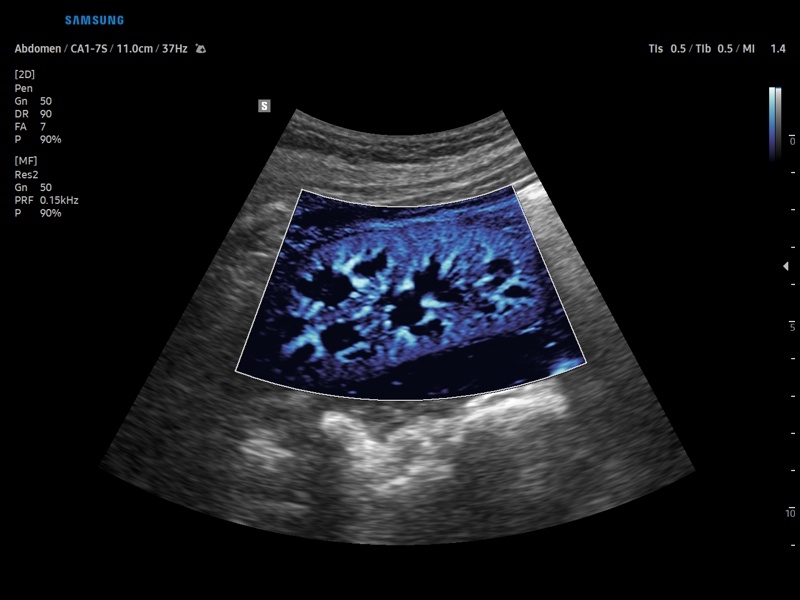

Ультразвуковой сканер V8-RUS является экспертным классом (премиальный уровень) и производится компанией Samsung Medison. Сканер V8 обеспечивает превосходное качество изображения благодаря использованию технологии Crystal Architecture™, которая включает в себя передовое аппаратное обеспечение, монокристальную технологию изготовления датчиков и сложную программную обработку ультразвуковых лучей.

• Цветной, энергетический и направленный энергетический допплер

• Абдоминальные исследования

• Модуль MV-Flow – программа (режим), позволяющая визуализировать кровоток в микроциркуляторном русле с высоким разрешением без использования контраста.

• Модуль LumiFlow – программа отображения кровотока с объемной графикой для лучшего понимания архитектоники сосудистого русла.